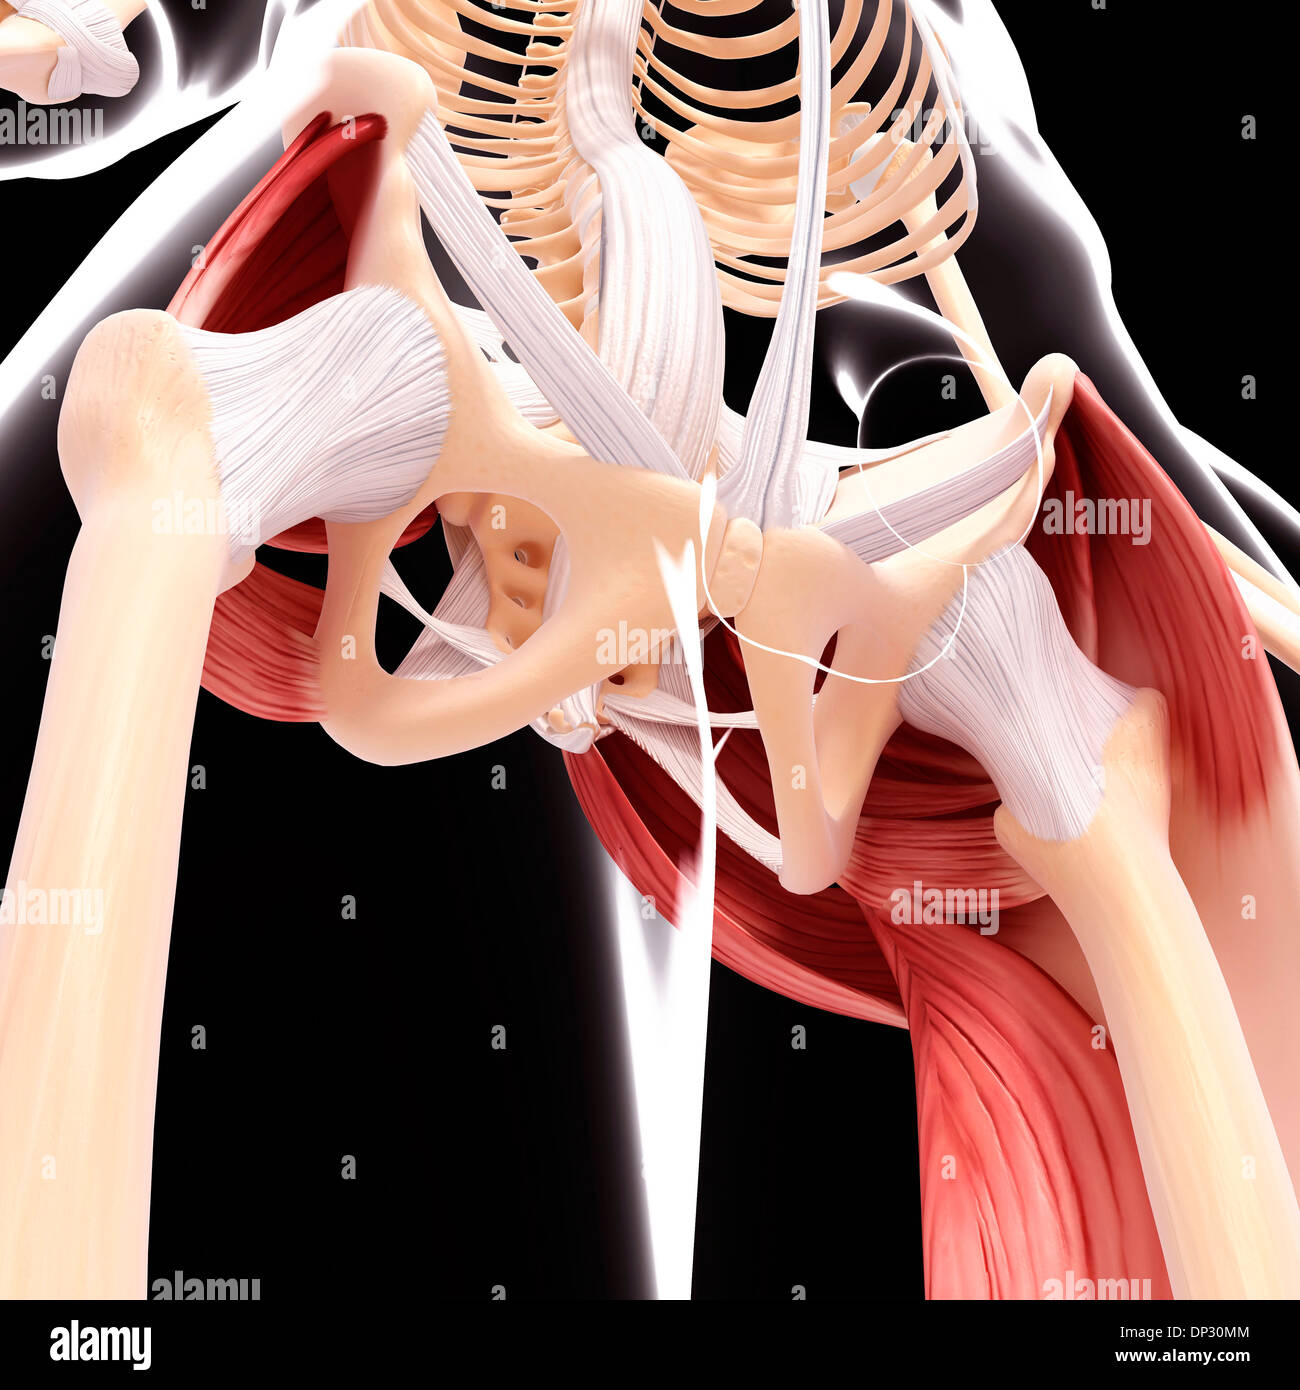

Human hip musculature, artwork Stock Photohttps://www.alamy.com/image-license-details/?v=1https://www.alamy.com/human-hip-musculature-artwork-image65219972.html

Human hip musculature, artwork Stock Photohttps://www.alamy.com/image-license-details/?v=1https://www.alamy.com/human-hip-musculature-artwork-image65219972.htmlRFDP30MM–Human hip musculature, artwork